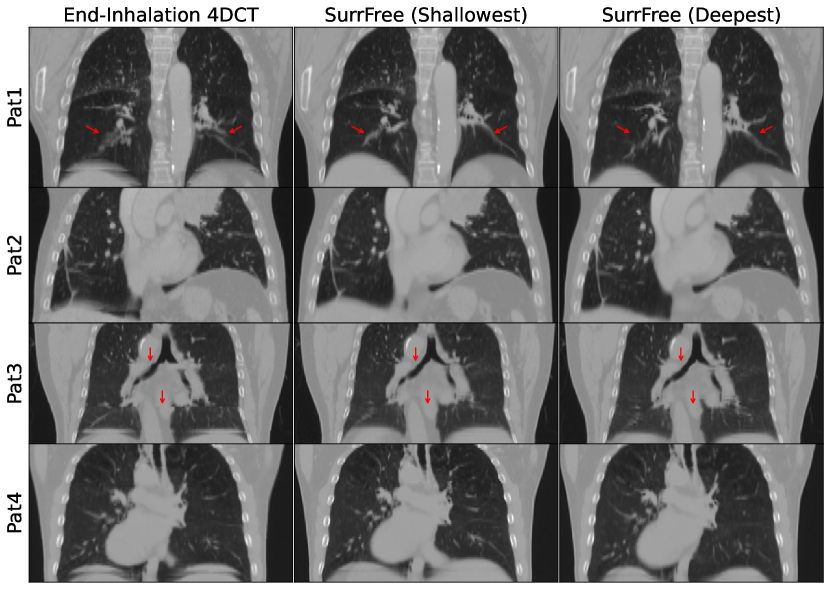

Our method was also demonstrated on four clinical 4DCT data, two of which (Pat1/Pat2) were from the ROSS-LC clinical trial [16] and the other two (Pat3/Pat4) were from the public TCIA 4D-Lung dataset [2]. Due to the absence of respiration signals used for 4DCT sorting, the surrogate-driven/optimized motion models could not be applied to these data retrospectively. Therefore, only the surrogate-free motion model was fit on the real patient data, and each slice was treated as an individual CT segment since no timing information was provided to determine which slices were acquired at the same time. Unlike the digital phantom data, there was no ground-truth for real data, so the end-inhalation images estimated by the surrogate-free motion model were visually compared with the end-inhalation phase of 4DCT. To show that our method could estimate irregular breathing motion, all the end-inhlation timepoints were identified according to the optimized surrogate signals and the two timepoints with the deepest and shallowest inhalation among them were selected for visual comparison.

Figure 3: Visual comparison between end-inhalation 4DCT and the deepest/shallowest end-inhalation images estimated by the surrogate-free motion model.

Fig.Β 3 shows the end-inhalation 4DCTs (left column), and the shallowest (middle) and the deepest (right) end-inhalation images estimated by the surrogate-free motion model for the four real patients. The sorting artefacts around the diaphragm were reduced in all the patients. For Pat1/3, the duplicate and discontinuity of certain structures were repaired by our method, as indicated by the red arrow. Fig.Β 3 also showed the variability of the end-inhalation phases due to the irregular breathing, i.e. the depth of end-inhalation could vary across breath cycles as indicated by the difference between the middle and the right column in Fig.Β 3. Our method could estimate the variation of breath which 4DCT could not estimate. Movies showing the estimated variable motion for all the patients and the phantom can be found in the supplementary.